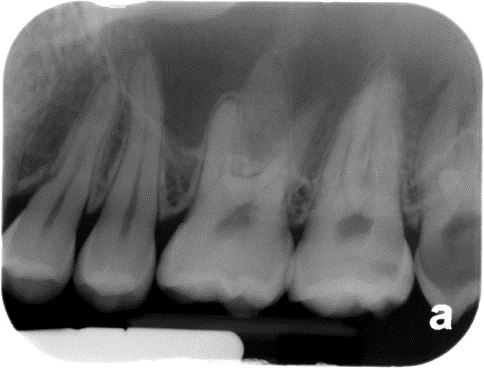

8. (Select ONE OR MORE correct answers)

Tooth 8.4 shows evidence of